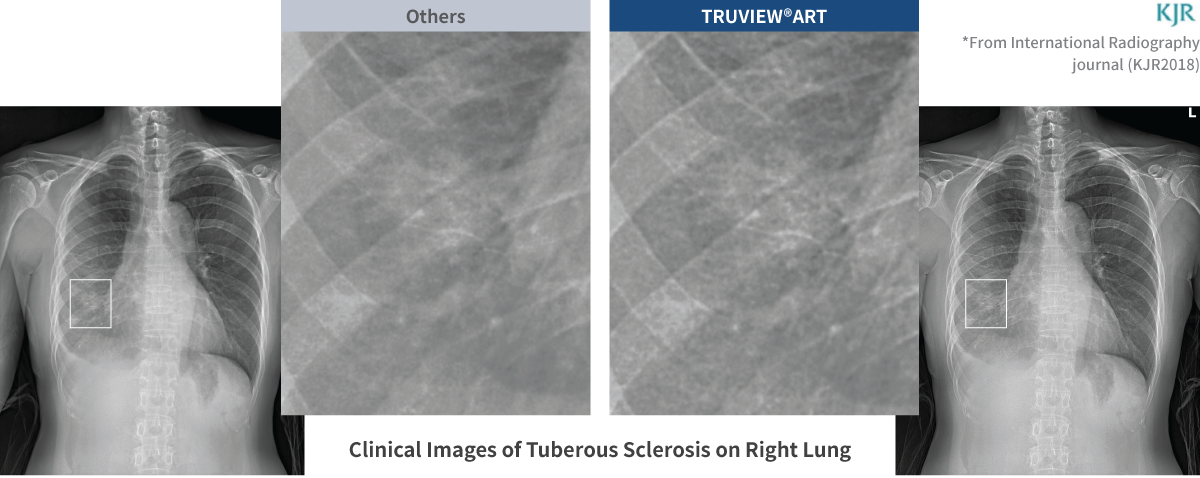

TRUVIEW®ART

RUVIEW®ART proporciona un contraste de imagen aumentado en un 30 % o más y una mejor capacidad de detección de microanomalías en los pulmones, el tórax y el corazón.

Visibilidad 2X para una claridad de diagnóstico excepcional